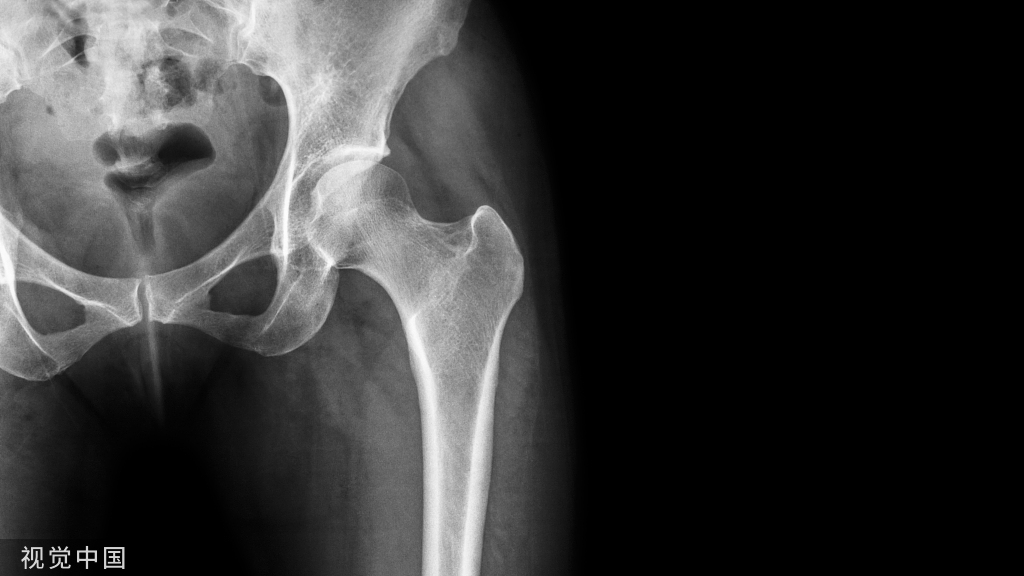

腰椎椎板板障厚度足够,可置入直径4.5mm的螺钉,穿透4层皮质钉住一侧关节突关节。双侧固定生物力学强度足够。